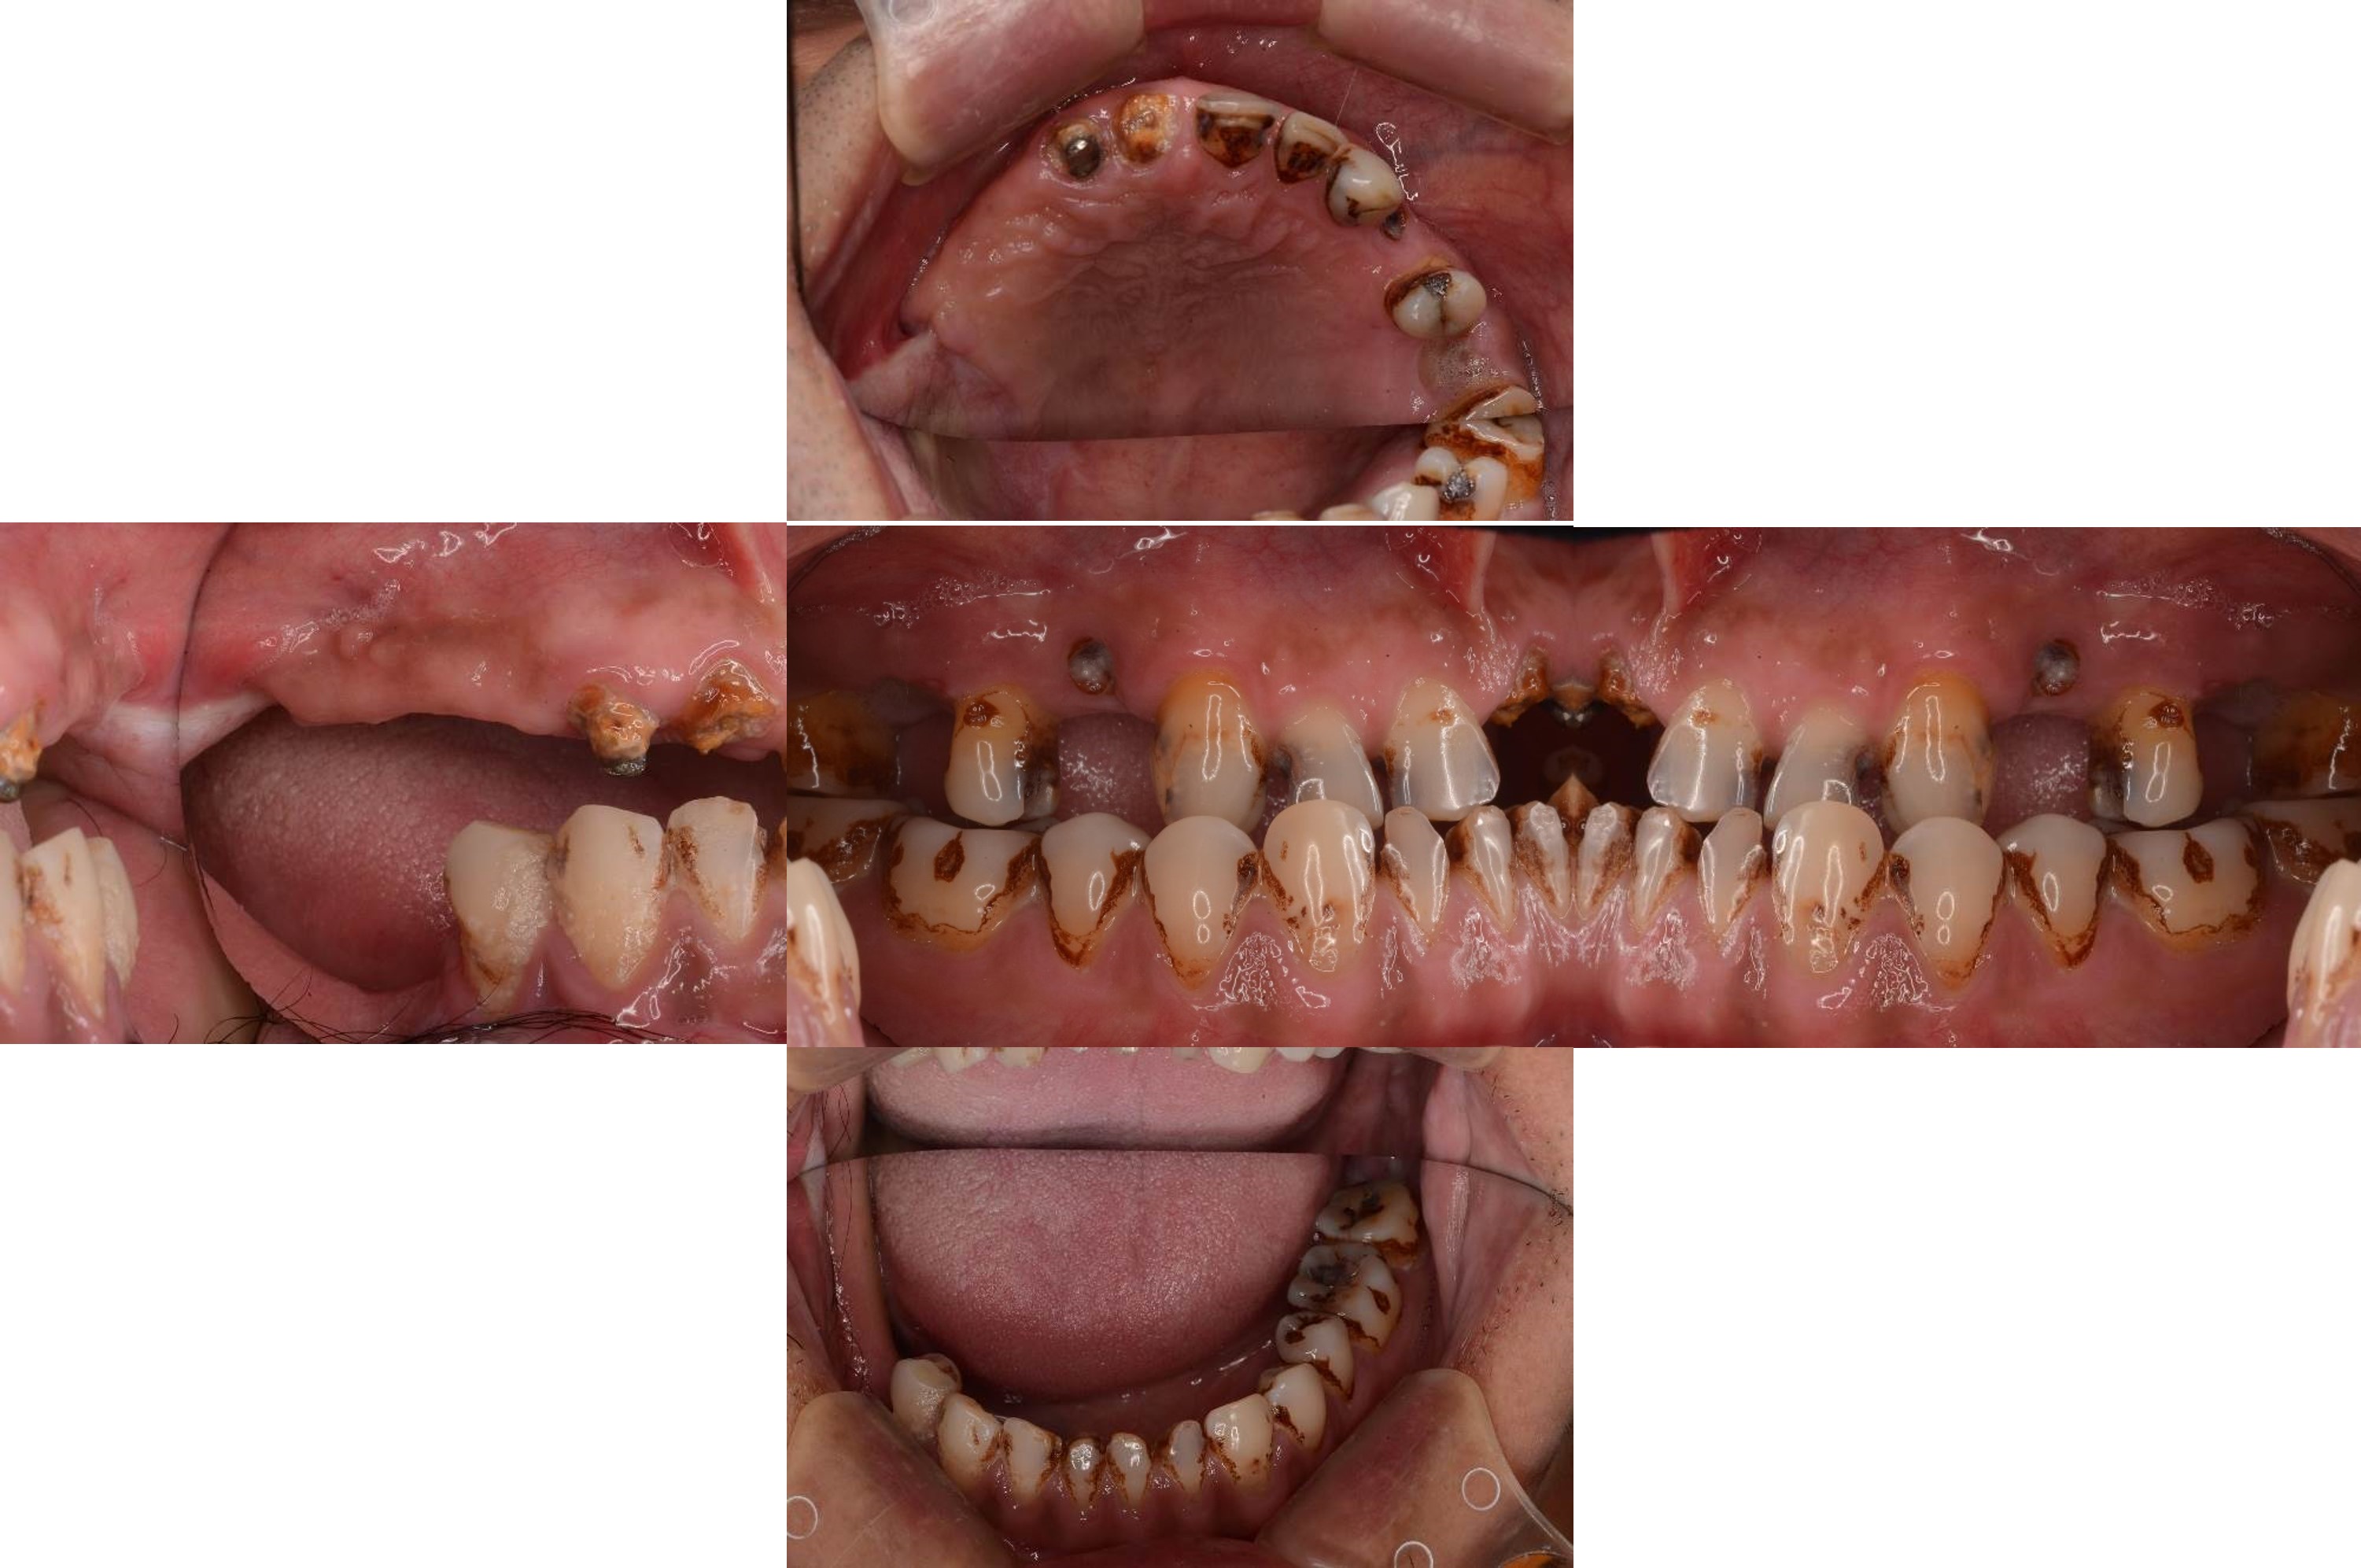

治療前上下顎因口外手術,造成咬合喪失

治療前,咬合喪失,磨耗

治療前,殘根與牙周支撐不良